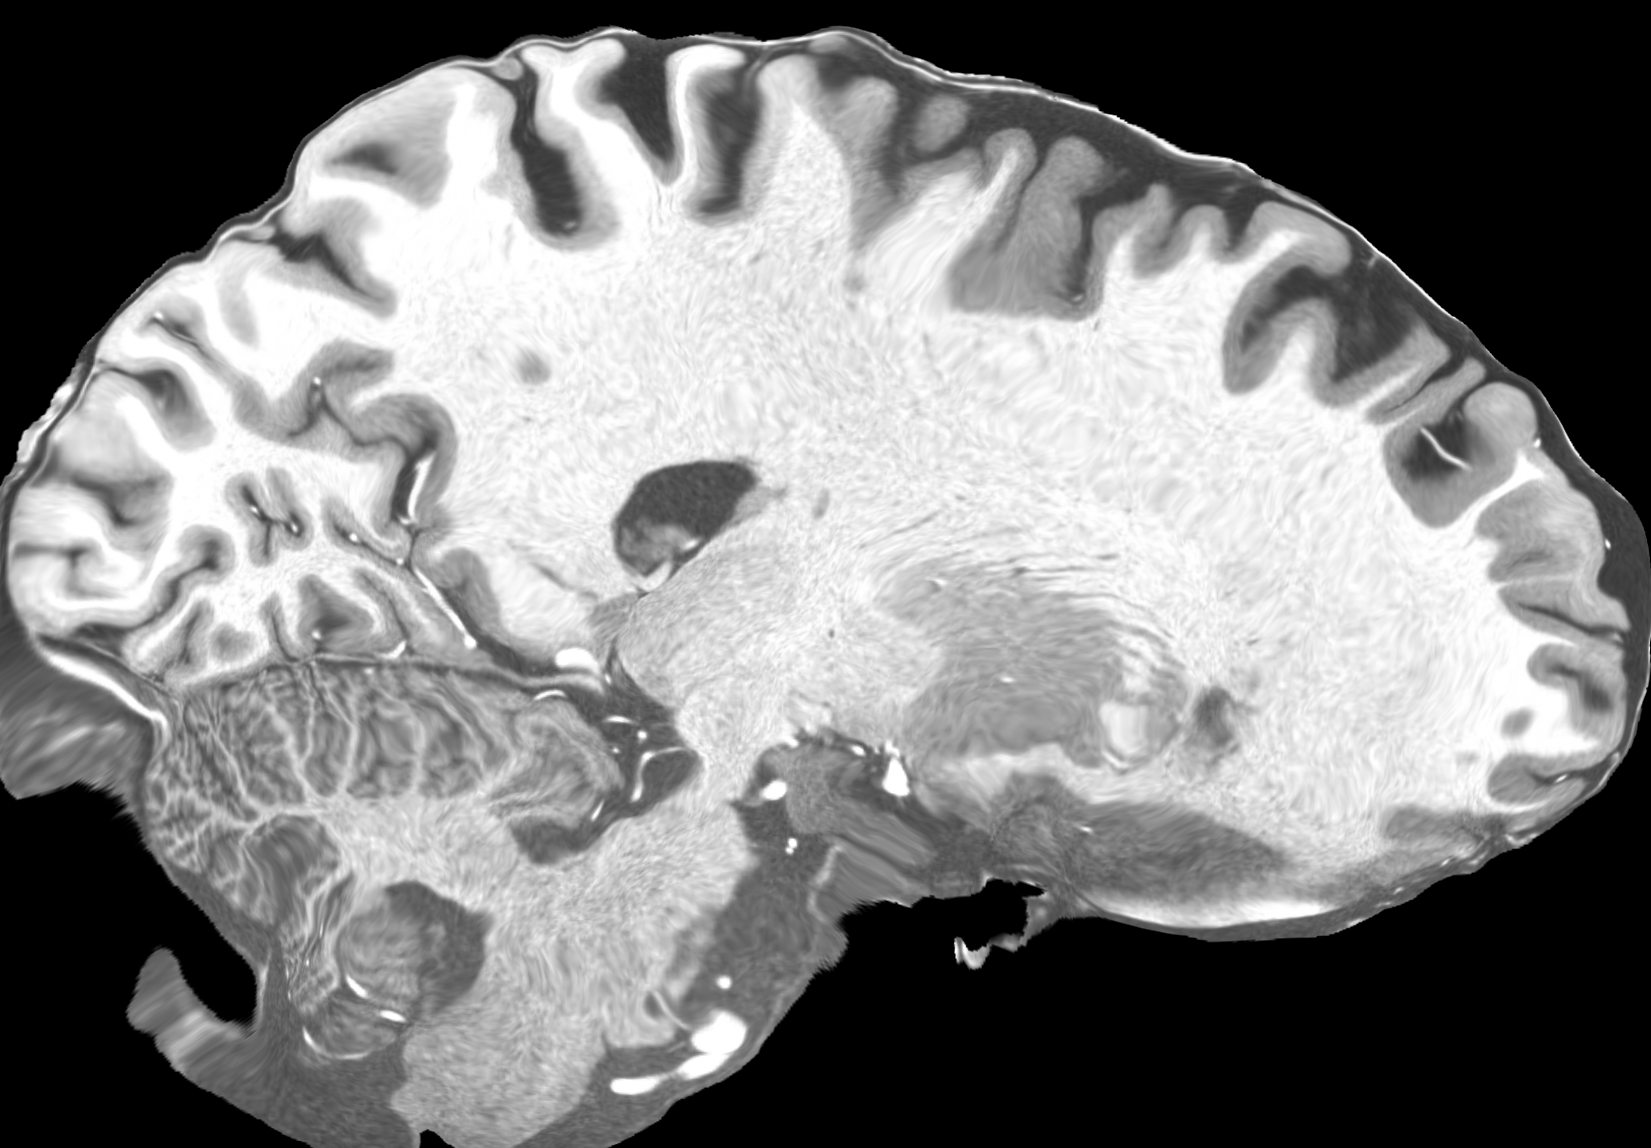

4.2 Registration to a 100 micron ex-vivo brain MRI volume

To showcase the efficacy of our method on real large scale images, we register a 250 in-vivo MRI image (Lüsebrink et al., 2017) to a 100 ex-vivo FLASH human brain volume (Edlow et al., 2019). This represents an inverse problem with more than 11.2B optimizable parameters (compared to 20M for clinical datasets), or 44.8GB of GPU memory. The entire problem does not fit on most GPUs, necessitating distributed multimodal registration. We optimize a composite transform - affine followed by a diffeomorphic mapping; details can be found in Section E.1. Multimodal deformable registration took 58 seconds on 8 NVIDIA A6000 GPUs, which is unprecedented at this resolution. Fig. 6 shows qualitative results, highlighting the ability to register highly detailed structures such as cerebellar white matter; these structures are not visible at macroscopic scales. The resultant advantages of performing registration at this scale can allow researchers to characterize the neuroanatomy at microscopic resolutions and allow morphometric analysis of cortical layers and subcortical nuclei among other structures.